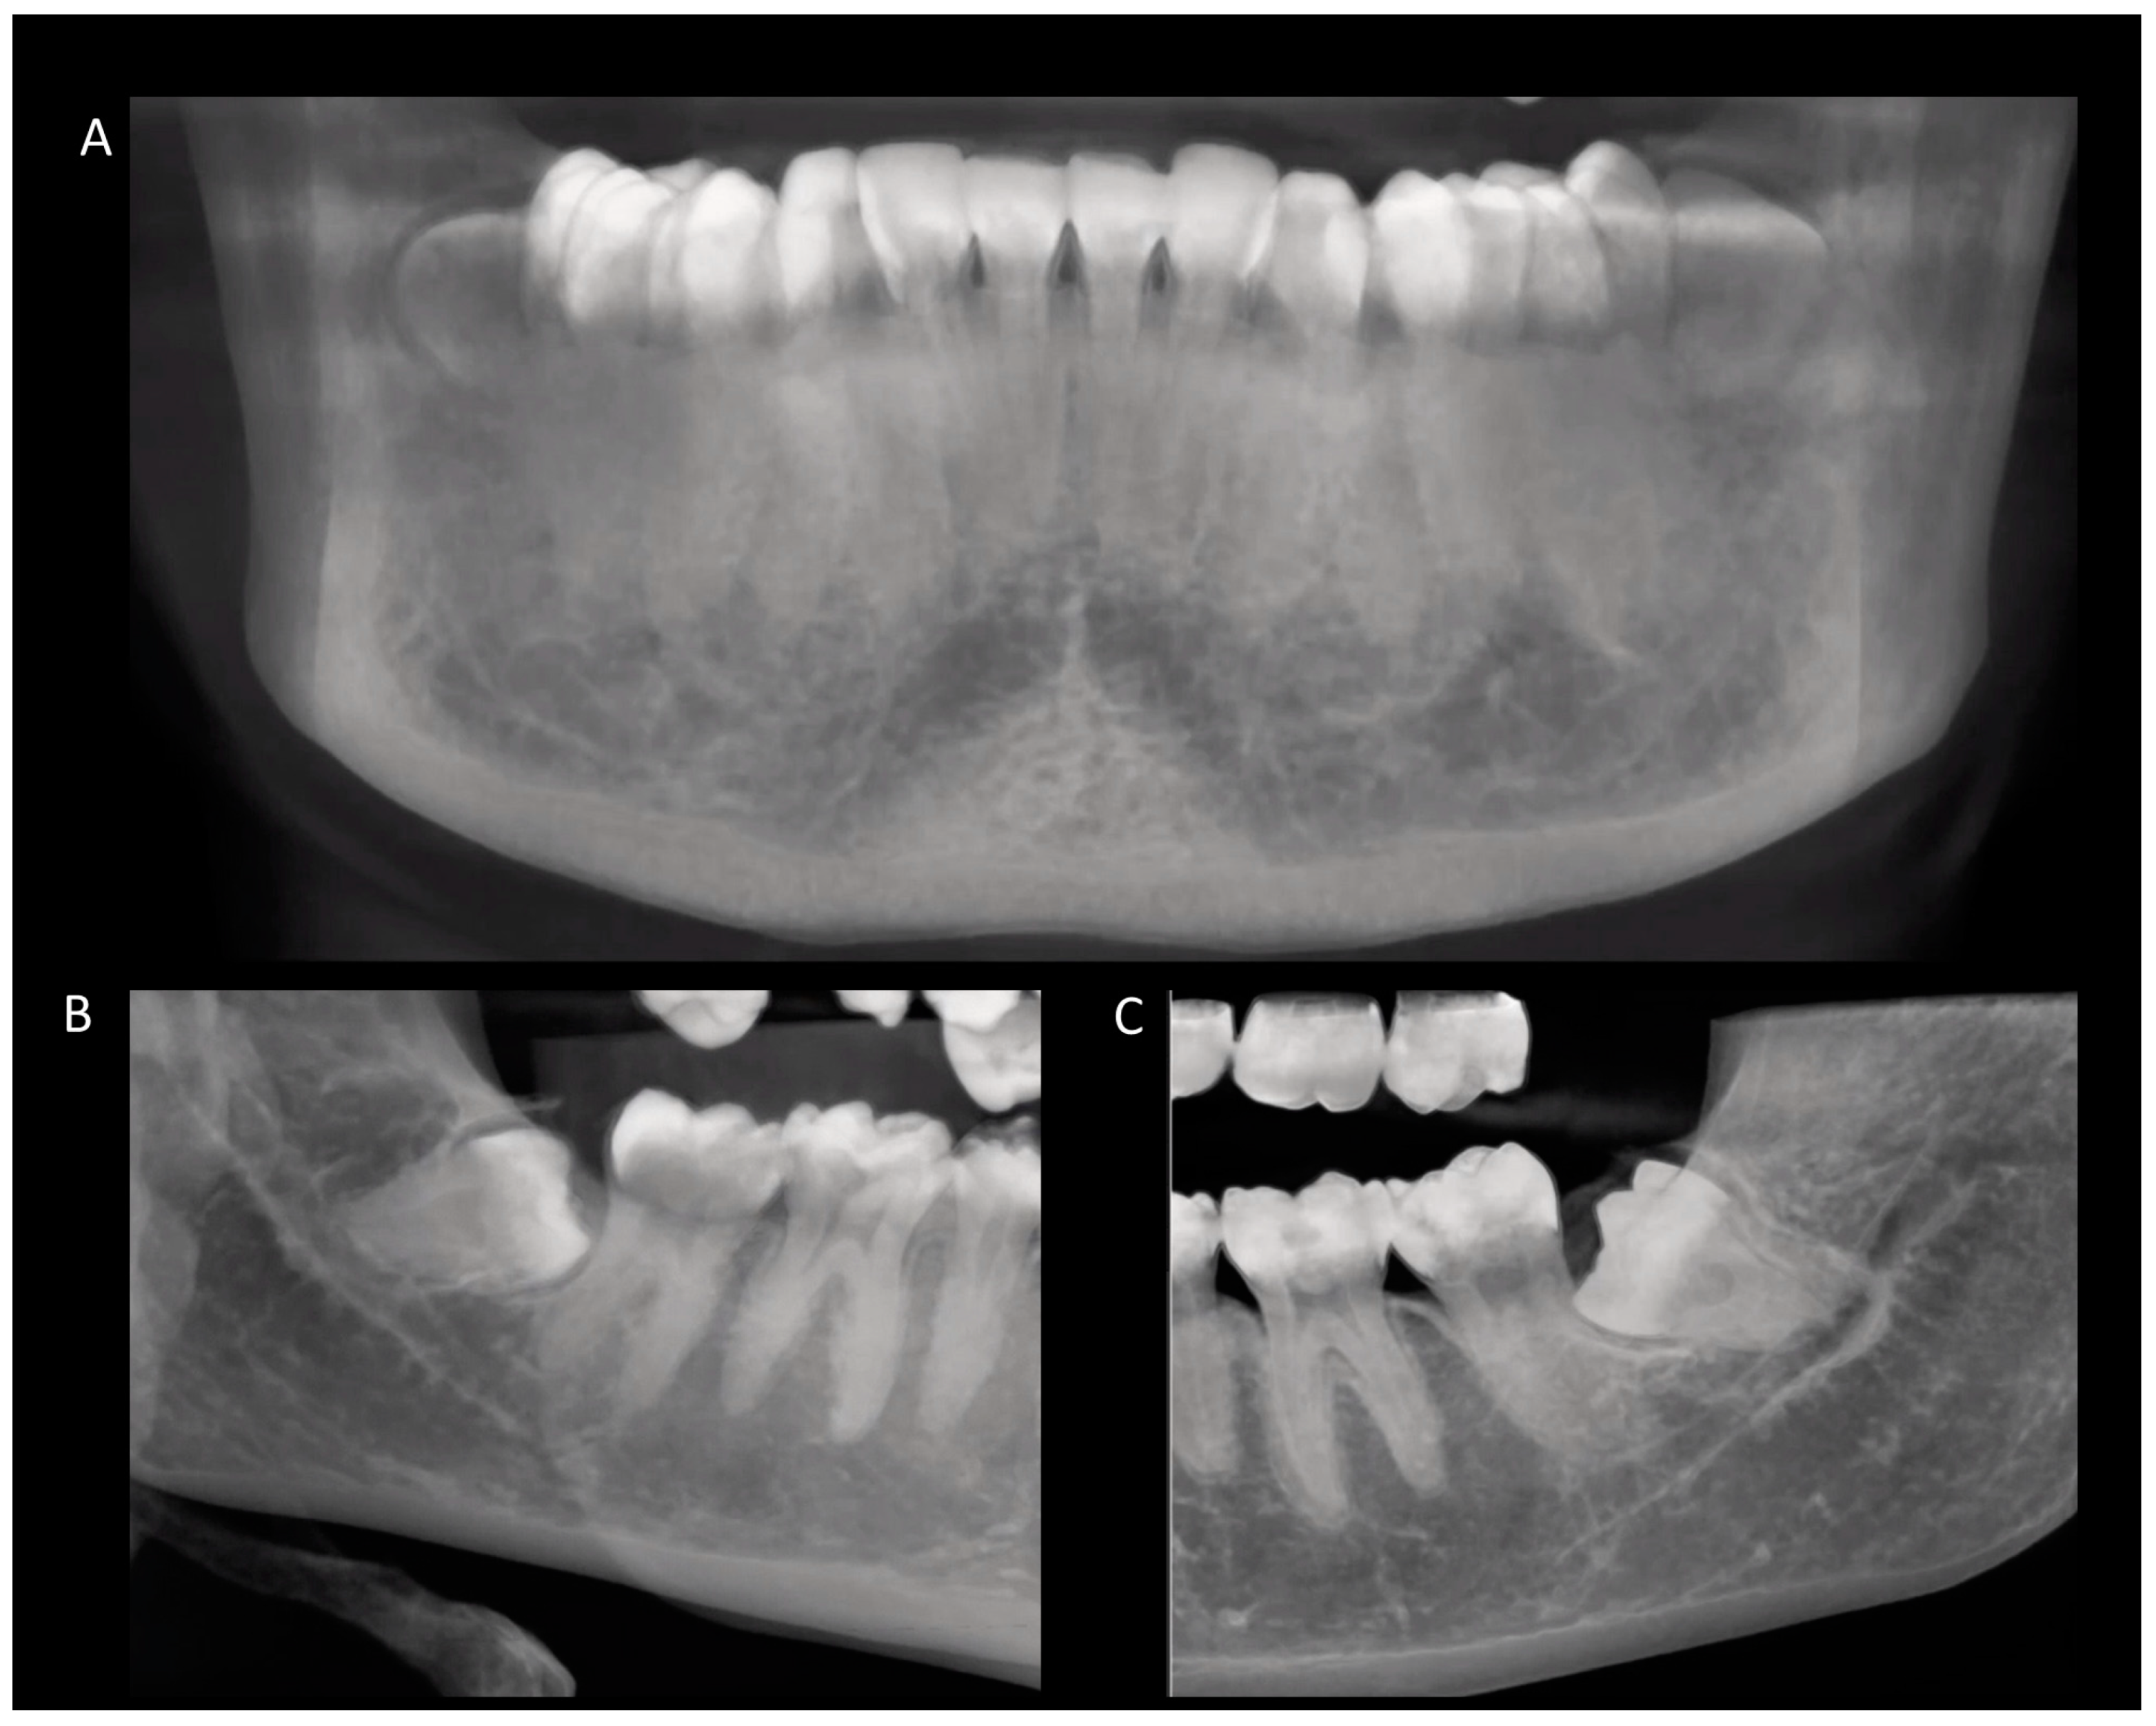

2. Materials and Methods

3.2. Positioning of Impacted Third Molars

3.4. Occurrence of External Root Resorption on the Distal Side of the Mandibular Second Molar